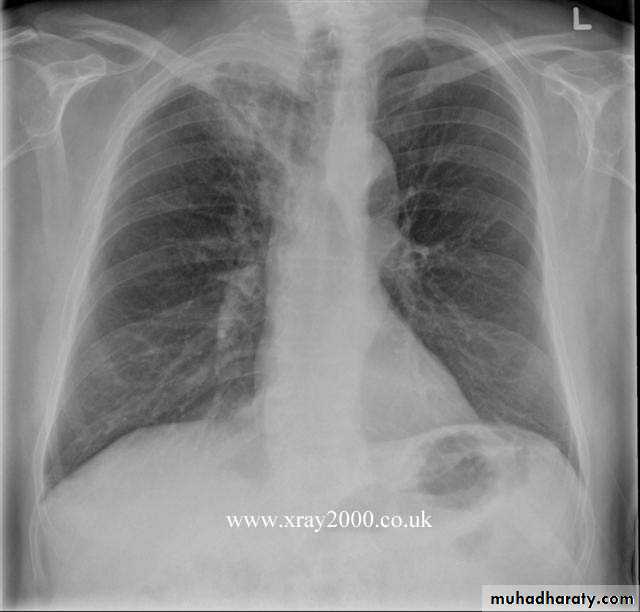

The main aims of investigations are to confirm the diagnosis, establish the histological cell type and define the extent of the disease.1-CXR: common radiological features of bronchial carcinoma;

Unilateral hilar enlargement.

Peripheral pulmonary opacity.

Lung, lobe or segmental collapse.

Pleural effusion.

Broadening of mediastinum, enlarged cardiac shadow, elevation of a hemidiaphragm.

Rib destruction.